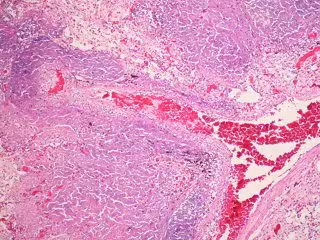

Investigadores españoles y alemanes crean un modelo en 3D de la 'nanomáquina' qu - FLICKER/ PULMONARY PATHOLOGY - Archivo

La tuberculosis es una enfermedad infecciosa que tiene una elevada tasa de fallecimiento, siendo una de las diez primeras causas de mortalidad en todo el mundo, y la cual impacta especialmente a personas con VIH y otras patologías que afectan al sistema inmunitario. De hecho, según datos de la Organización Mundial de la Salud (OMS), 10 millones de personas enfermaron de tuberculosis en 2017 en todo el mundo, 1,6 de las cuales fallecieron.